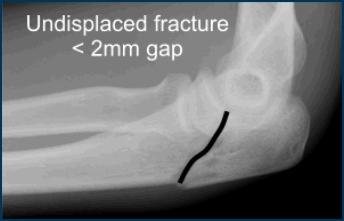

Mouseover image if you

can't see the fracture.

Treatment depends on whether the fracture is displaced or undisplaced.

If the fracture is undisplaced and the pieces have not moved far apart, then treatment is non operative.

Non operative treatment is usually reserved for undisplaced fractures (<2mm) or patients not fit for surgery.